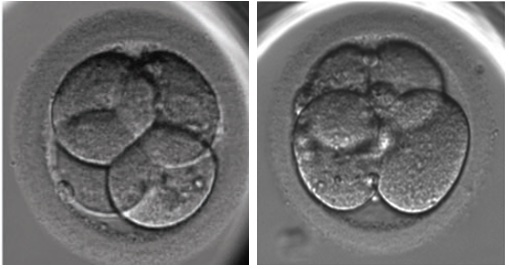

Cell number is considered to be the most important factor in determining the potential for a cleavage stage embryo. Each cell divides at a certain rate to give a total number by a certain day. On day 2 that number is 4 cells and on day 3 it’s 8 cells. Not all embryos will have these numbers on these days, some might go a bit slower (or faster!) and that’s okay. But an embryo with an ideal number typically has the best chance.

Four and eight cells

Symmetry is how evenly sized each cell in a cleavage stage embryo is. If all the cells are the same size, this is a good sign! It means that they divided equally and all the “stuff” inside the cells was split up properly. Otherwise, in the case where many of the cells aren’t evenly sized, this is an indication of poor embryo quality. Often high fragmentation and poor symmetry correlate with each other.

Cell symmetry